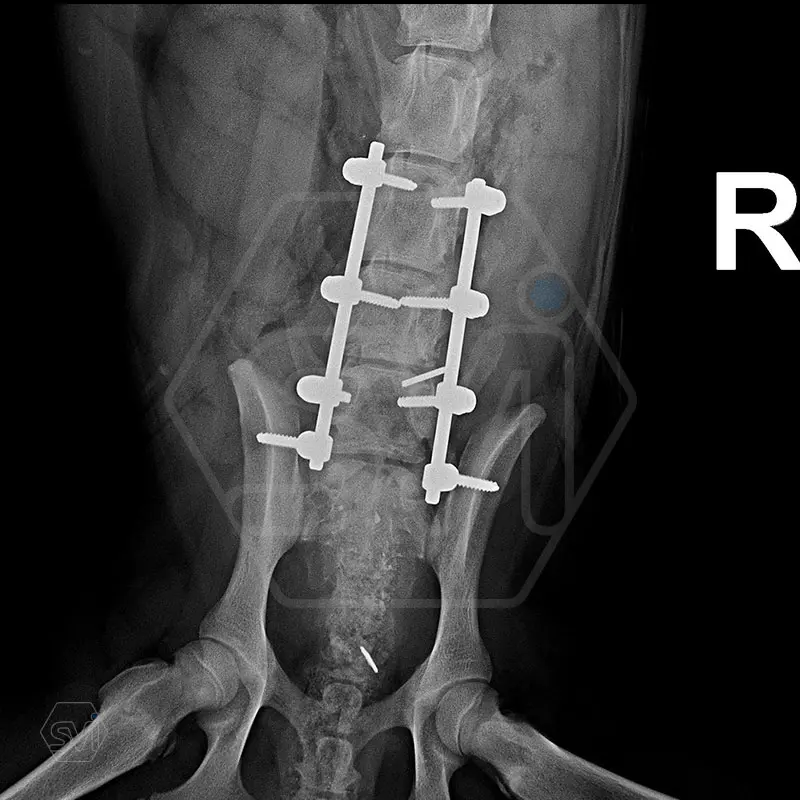

L6 vertebral body fracture fixation with 2.7-mm SOP-LC system

We performed a laminectomy of L7 and then performed fixation with a 4-4 clamp, bilateral 2.7-mm SOP-LC system. Control x-rays were taken at 6 and 12 weeks after surgery. Based on the video, in our opinion, the dog has recovered… :)